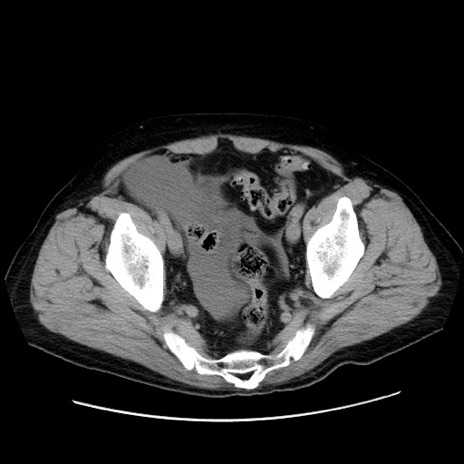

症例30(横断像)

【症例】80歳代男性

【主訴】臍周囲痛

【現病歴】約6時間前から臍下部痛が出現。次第に腹部膨隆・背部痛も生じてきたため来院。背部痛の場所は変化しない。

【身体所見】意識清明、BT 36.3℃、BP  131/87mmHg、P 87bpm、SpO2 100%(RA)、臍周囲自発痛・圧痛あり、反跳痛なし、自発痛部位に一致して板状硬あり、腹部膨隆、腸雑音減弱、CVA tenderness両側陰性。